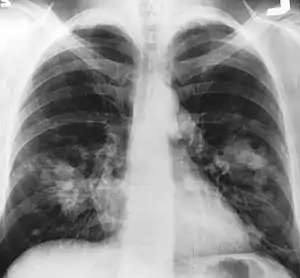

| An X-ray scan indicating abnormal masses in the lungs. | |